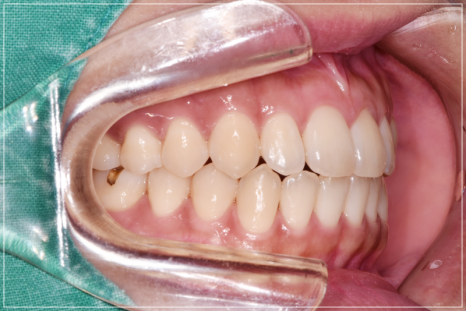

입이 안 다물어지는 문제를 해결한 모습

입술이 붕 뜨는 고민을 해결한 모습

앞니가 안 다물어지는 상태를 개선한 모습

개방교합이 심해 장치 후 교정을 진행해야 하는 케이스입니다.

가지런히 정돈된 치열과 개방교합이 개선된 모습